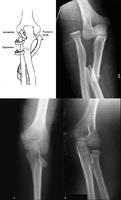

孟氏骨折

尺骨上1/3骨折合并桡骨小头脱位称孟氏骨折。孟氏骨折多发生于青壮年及小儿,直接或间接暴力皆可引起。1914年意大利外科医生Monteggia最早报导了这种类型骨折,故称孟氏骨折。

X 线检查:前臂正、侧位片可以确诊。应包括肘关节以免漏诊,注意肱桡关节的解剖关系,必要时可拍健侧 X 线片作对照。凡尺骨上段骨折,而 X 线片未见到桡骨头脱位时,应按此种骨折处理,因为桡骨头脱位后有时会自行复位。

根据患者有明显外伤史,患肢疼痛,活动受限,局限性压痛。Х线片可确定骨折部位及移位情况。